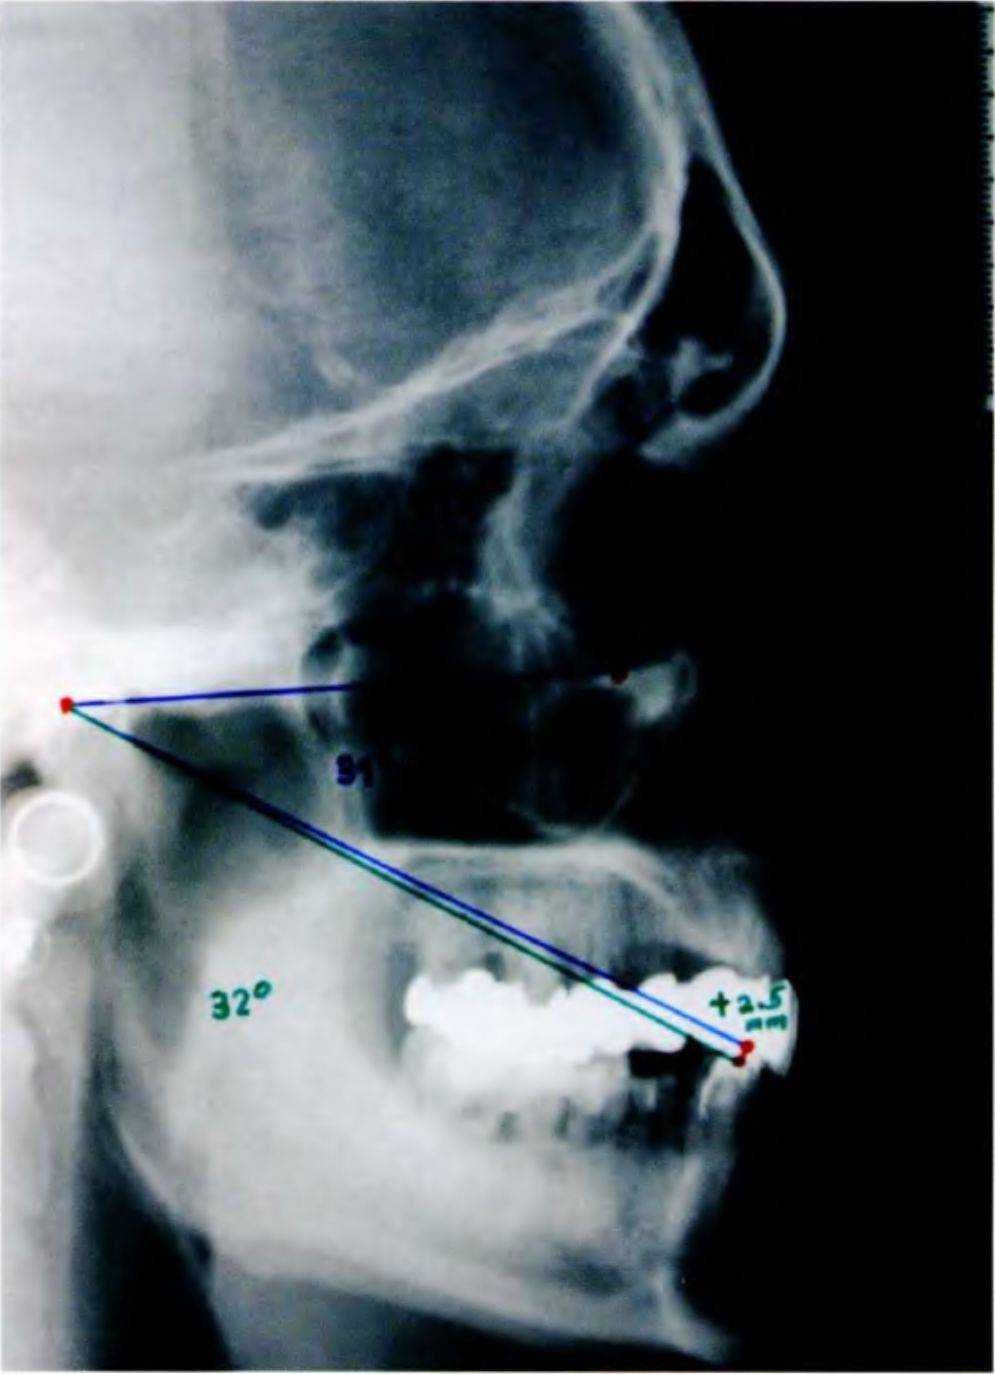

сообщили, что угол между сопряженной плоскостью и осевой глазничной плоскостью (СП-ОГП) почти всегда одинаков из-за центрального направления роста относительно сопряженной плоскости. У подростков этот угол составляет 31,3°, а у взрослых - 32°. Данный показатель является ключевым для определения вертикального расстояния, которое можно перенести в артикулятор (рис. 6-4а и 6-4Ь, табл. 6-1).

Рис. 6-Бд. Функциональный анализ цефалограммы

Боковую цефалограмму для функционального анализа получают при расположении челюстей в центральном соотношении (рис. 6-5д). В данном случае угол СП-ОГП составил 31°. Таким образом, окклюзию можно увеличить так, чтобы угол СП-ОГП увеличился на 1°.

Для передачи этого показателя в артикулятор сопряженную плоскость нарисовали так, чтобы угол

СП-ОГП составил 32° (рис. 6-5h). После этого измерили расстояние между двумя линиями на уровне режущего края нижнего переднего зуба, которое составило 2,5 мм.

Как можно увидеть в области основания носа, увеличение изображения на боковой цефалограмме составляет 1:1,10. Данную шкалу использовали для определеня степени увеличения окклюзии, с учетом чего откорректировали разделитель (4 мм). Таким образом, полученное значение перенесли в артикулятор и откорректировали резцовый штифт.